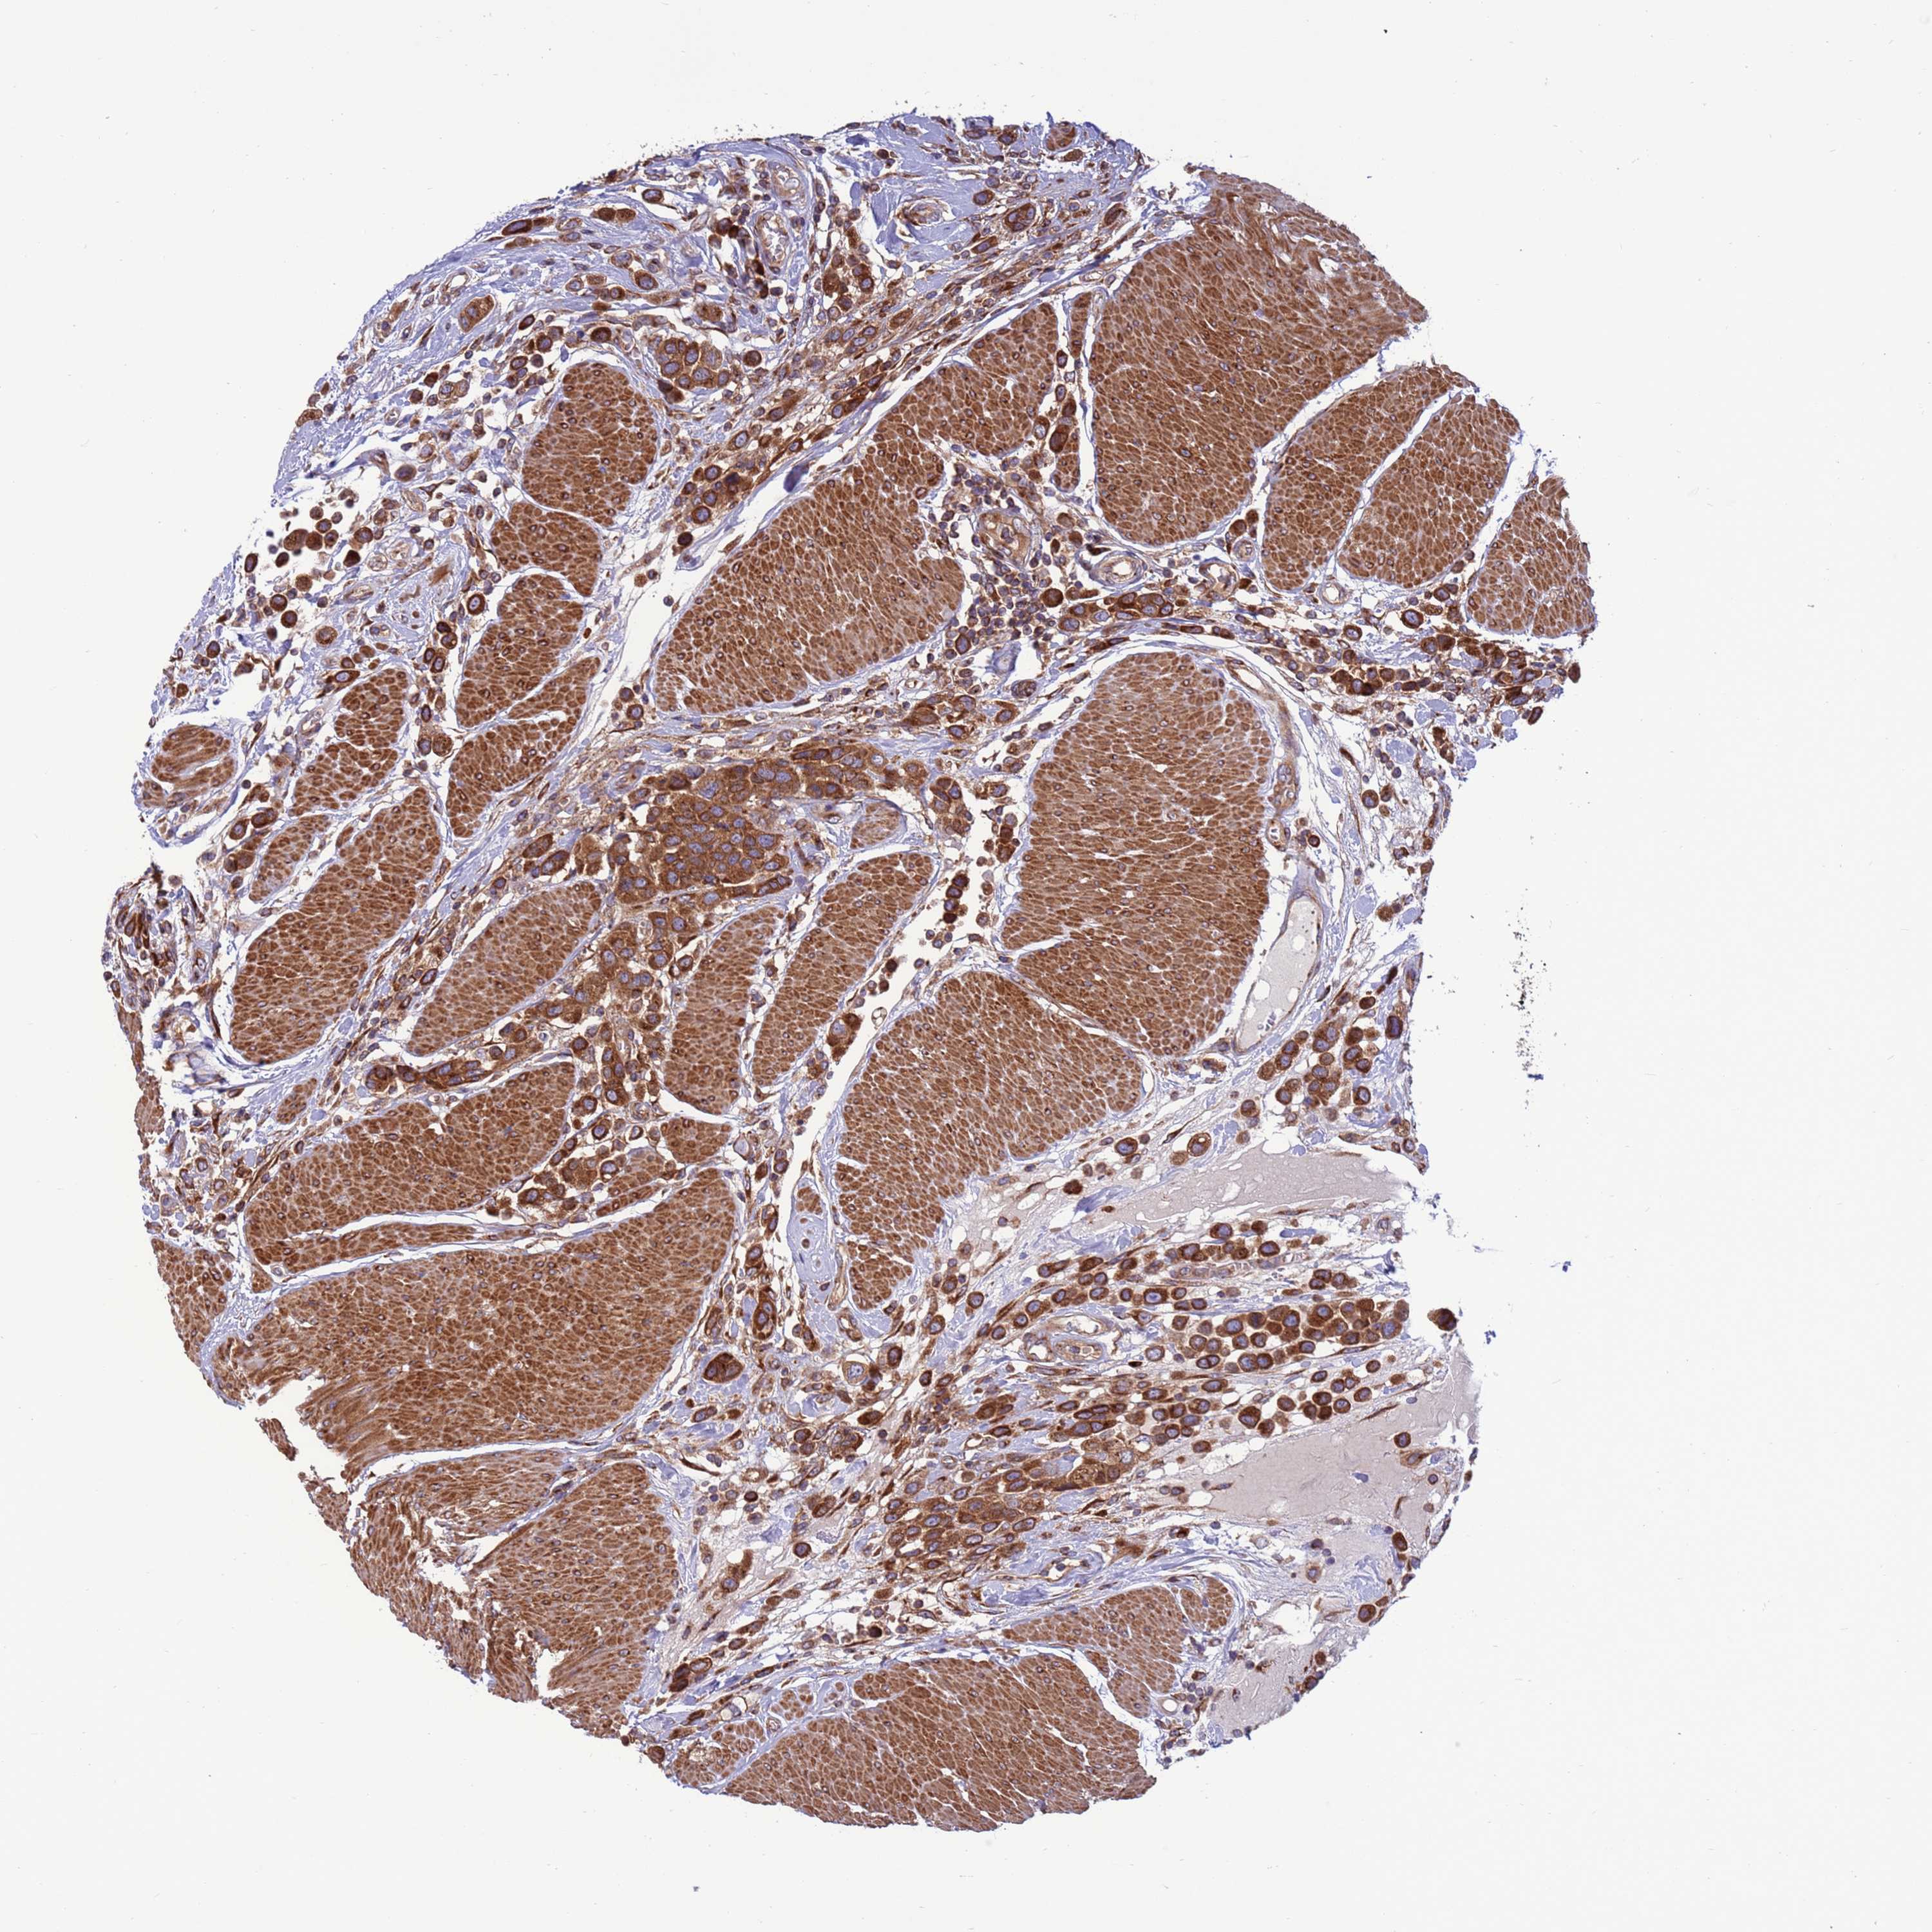

UROTHELIAL CANCER - Protein expressioni

A mouse-over function shows sample information and annotation data. Click on an image to view it in a full screen mode. Samples can be filtered based on level of antibody staining by selecting one or several of the following categories: high, medium, low and not detected. The assay and annotation is described here.

Note that samples used for immunohistochemistry by the Human Protein Atlas do not correspond to samples in the TCGA dataset.

Antibody stainingi

Antibody staining in the annotated cell types in the current human tissue is reported as not detected, low, medium, or high, based on conventional immunohistochemistry profiling in selected tissues. This score is based on the combination of the staining intensity and fraction of stained cells.

Each image is clickable and will lead to virtual microscopy that enables deeper exploration of all samples and also displays staining intensity scores, fraction scores and subcellular localization as well as patient and tissue information for each sample.

Antibody HPA047818

Staining

High

Medium

Low

Not detected

Intensity

Strong

Moderate

Weak

Negative

Quantity

>75%

75%-25%

<25%

None

Location

Nuclear

Cytoplasmic/membranous

Cytoplasmic/membranous,nuclear

Urothelial carcinoma, Low grade

Urothelial carcinoma, High grade